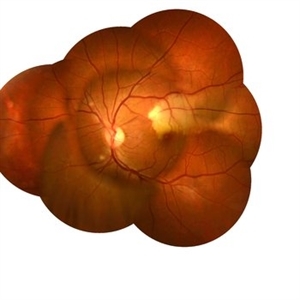

Retina Images (13 files)

Retina Images (13 files)